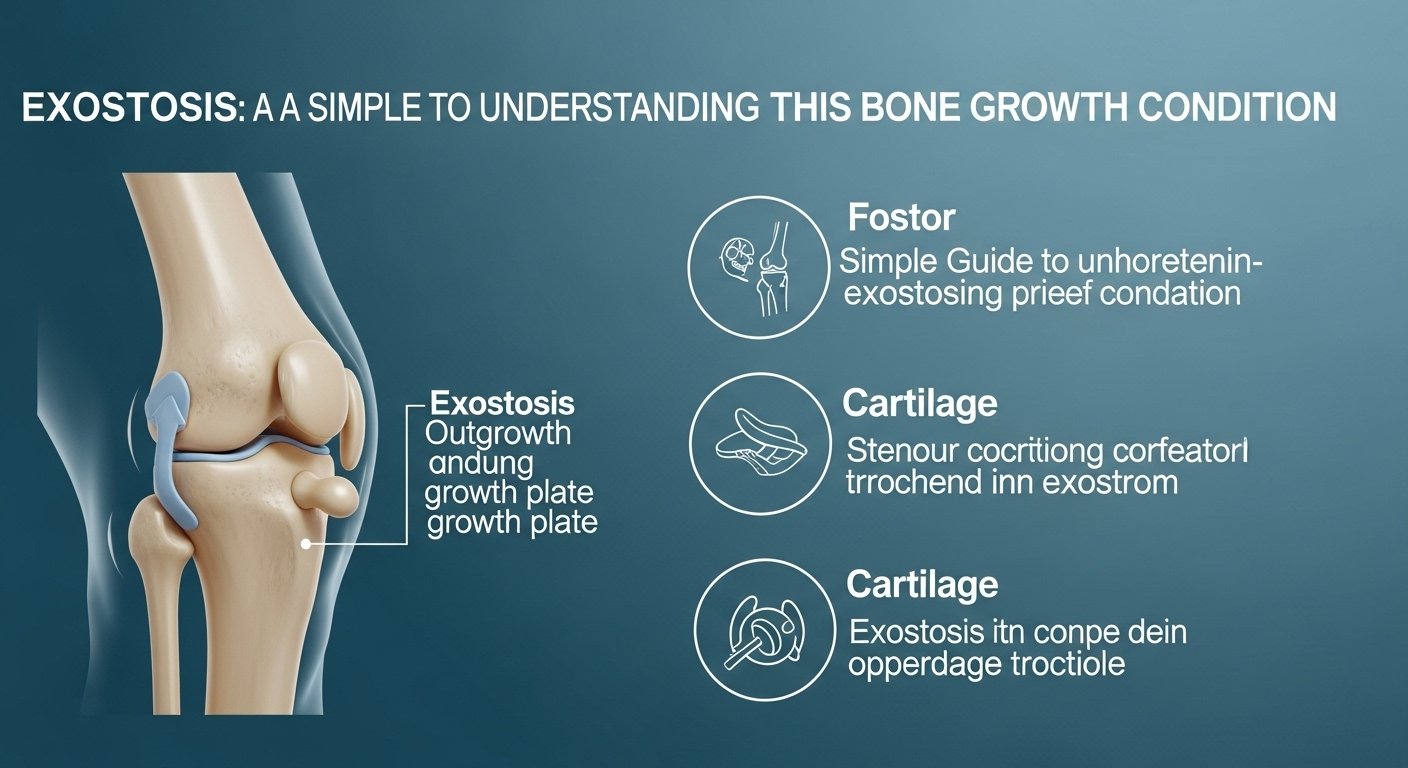

What Is Exostosis?

Exostosis refers to an abnormal growth of bone on top of a normal bone. Think of it as a little extra bump or lump made of bone tissue. These bony growths can appear on different parts of the body, like the jaw, ear canal, knee, or heel. Sometimes they grow slowly over time and go unnoticed until they start causing discomfort or begin pressing against something nearby, like muscles, skin, or nerves. While most exostoses (that’s the plural form) are non-cancerous, they should still be checked by a doctor to make sure they aren’t caused by another condition. Many people live with a small exostosis and never need treatment, though in some cases, removal is necessary.

Different Types of Exostosis

There are several types of exostosis, depending on where they appear and what causes them. One common type is osteochondroma, which usually appears near the growth plates of children and teens, often around the knee. Another type is subungual exostosis, which shows up under a toenail or fingernail and can cause pain or nail problems. Surfer’s ear, which we’ll talk more about later, is a form of exostosis in the ear canal caused by cold water exposure. There’s also buccal exostosis, found on the jawbone near the molars. Each type looks and feels different but they all have one thing in common—they’re made from bone growing in places where it typically shouldn’t.